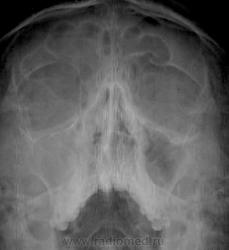

Верхнечелюстной и лобный синусит справа, катарально-отечный верхнечелюстной синусит слева

Обозвал бы правосторонним гемисинуситом.

правосторонний гемисинусит